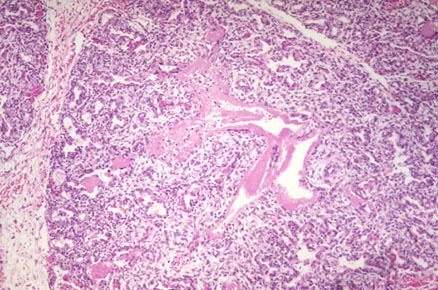

Low power photomicrographic of HMD showing immature lung with hyaline membranes.